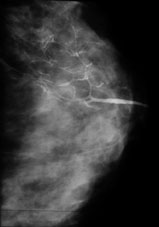

Galactographie

La galactographie est un examen radiologique indispensable à réaliser quand il y a un écoulement anormal par un seul pore du mamelon (sérosité, sang). On injecte alors un produit de contraste à base d'iode, par le pore du galactophore concerné (c'est un canal qui sécrète le lait), pour faire ressortir ses contours.